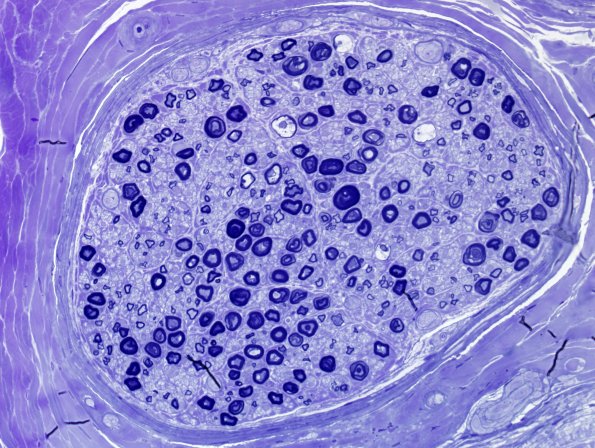

Washington University Experience | PERIPHERAL NEUROPATHY | 0 PNS ARTIFACTS | 12D4 Artifact, crush Deeper sections Plastic 40X 2 (2)a.jpg

Deeper sections show much less artifact. (Toluidine blue stained one micron thick plastic embedded sections)